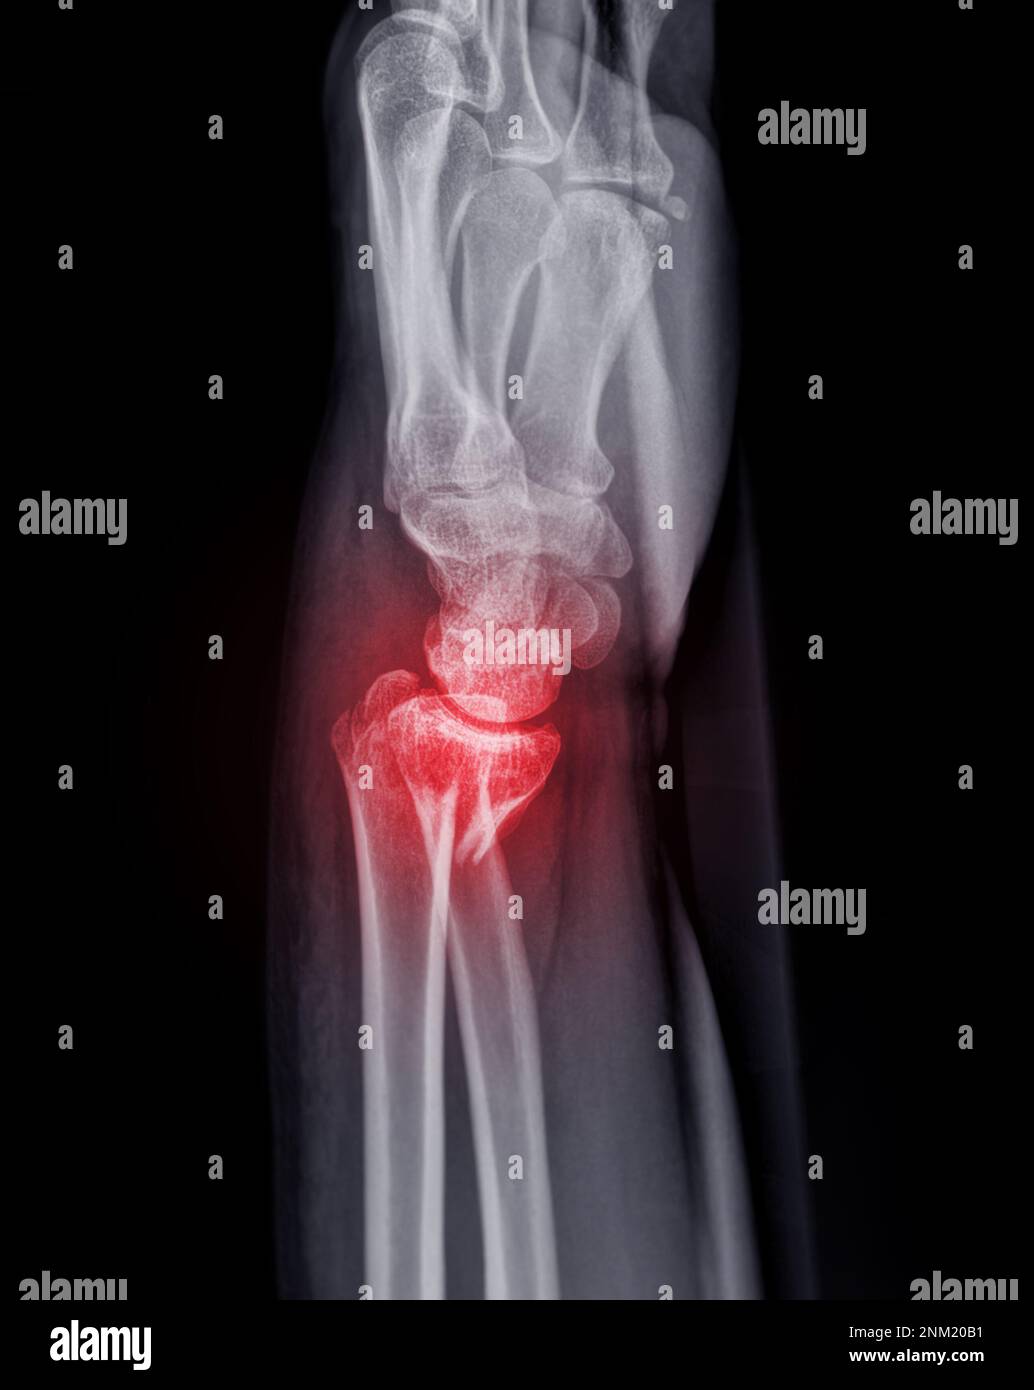

Image radiographique de l'articulation du gauche AP et vue Fracture Du Poignet Gauche Fracture du poignet chez l’adulte. La plupart des fractures du poignet. les fractures du poignet sont généralement dues à une chute sur une main tendue. Dans 50 % des cas,. Il existe 2 types de traitement : douleurs et gonflement du poignet sont les symptômes les plus fréquents de la fracture du poignet. Un poignet fracturé est douloureux,. Fracture Du Poignet Gauche.

Fracture Du Poignet Gauche . les fractures du poignet localisées à l’extrémité inférieure du radius chez l’adulte sont très fréquentes. la fracture du poignet est généralement due à une chute sur une main tendue: cet article fait partie du dossier : Fracture du poignet chez l’adulte. les fractures du poignet sont généralement dues à une chute sur une main tendue. Quelles sont les principales causes des fractures du poignet ? Le radius se casse alors près du poignet, et l’extrémité cassée du radius est déplacée vers le Ces fractures peuvent généralement être identifiées sur des radiographies, mais une tomodensitométrie est parfois nécessaire. Combien de temps garder le plâtre ? c'est surtout l'extrémité du radius ou du scaphoïde qui se casse en cas de fracture au poignet. La plupart des fractures du poignet. Le poignet ne supporte pas le poids du corps et se brise. Il existe 2 types de traitement : douleurs et gonflement du poignet sont les symptômes les plus fréquents de la fracture du poignet. une fracture du poignet est une fracture de l’un des os de votre poignet.

Fracture Du Poignet Gauche Quelles sont les principales causes des fractures du poignet ? Combien de temps garder le plâtre ? Quelles sont les principales causes des fractures du poignet ? c'est surtout l'extrémité du radius ou du scaphoïde qui se casse en cas de fracture au poignet. une fracture du poignet est une fracture de l’un des os de votre poignet. cet article fait partie du dossier : La plupart des fractures du poignet. Ces fractures peuvent généralement être identifiées sur des radiographies, mais une tomodensitométrie est parfois nécessaire. douleurs et gonflement du poignet sont les symptômes les plus fréquents de la fracture du poignet. les fractures du poignet localisées à l’extrémité inférieure du radius chez l’adulte sont très fréquentes. Dans 50 % des cas,. la fracture du poignet est généralement due à une chute sur une main tendue: Le radius se casse alors près du poignet, et l’extrémité cassée du radius est déplacée vers le Le poignet ne supporte pas le poids du corps et se brise. Il existe 2 types de traitement : les fractures du poignet sont généralement dues à une chute sur une main tendue.